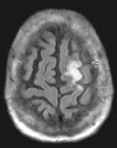

Routine FLAIR MRI images (left) cannot differentiate between acute infarcts and chronic ischemic changes/infarcts. The diffusion MRI (right) clearly demonstrates an acute infarct in the left frontoparietal region (the chronic changes do not "light up" on the diffusion study).